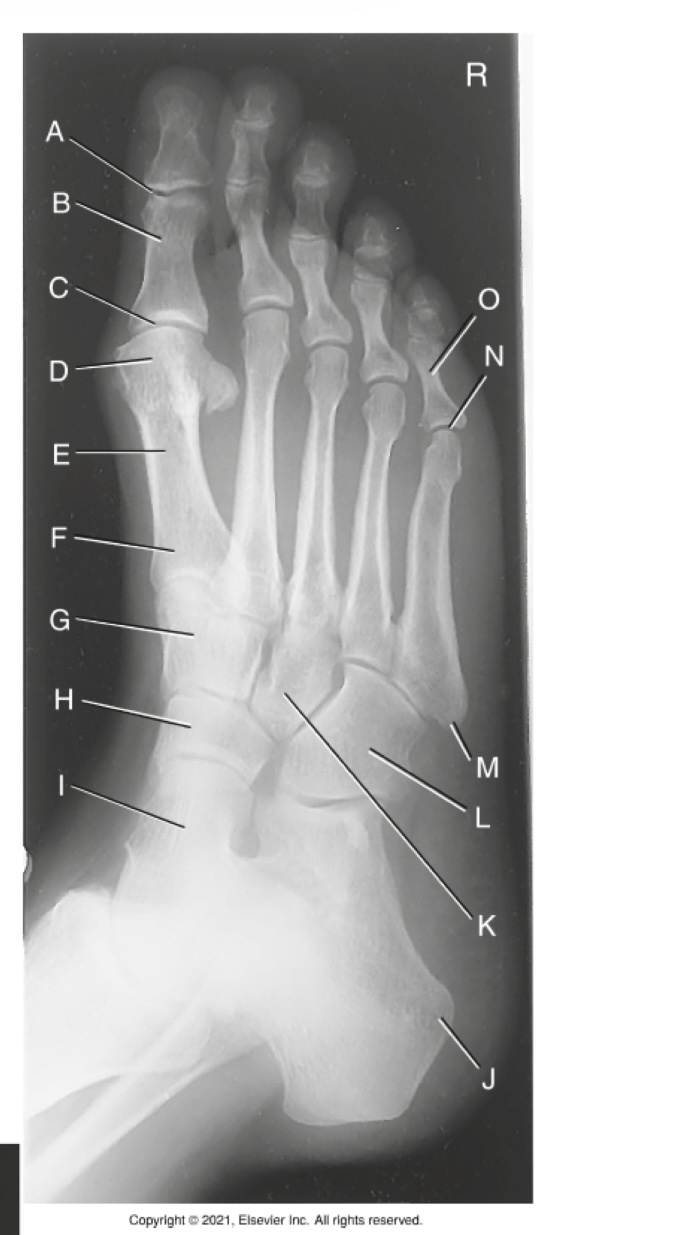

(AP OBLIQUE FOOT) what is A?

medial cuneiform

what is B?

intermediate cuneiform

what is C?

metatarsals

what is D?

Tuberosity (of the fifthmetatarsal

what is E?

lateral cuneiform

what is F?

cuboid

what is G?

calcaneous

what is H?

navicular

what is I?

talus

what is J?

sinus tarsi